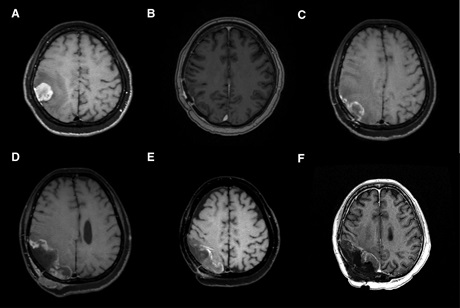

一位78岁女性上唇肿块形成3个月,经过检查发现,在左上中切牙至尖牙区域的唇颊沟处有一形态不规则的肿瘤样肿物。活检后,诊断为乳头状囊腺癌。患者拒绝接受手术治疗、化疗及放疗。之后肿瘤在三年半的时间里逐渐增大,在拒绝接受手术的情况下,患者最终同意接受硼中子俘获疗法(BNCT)。